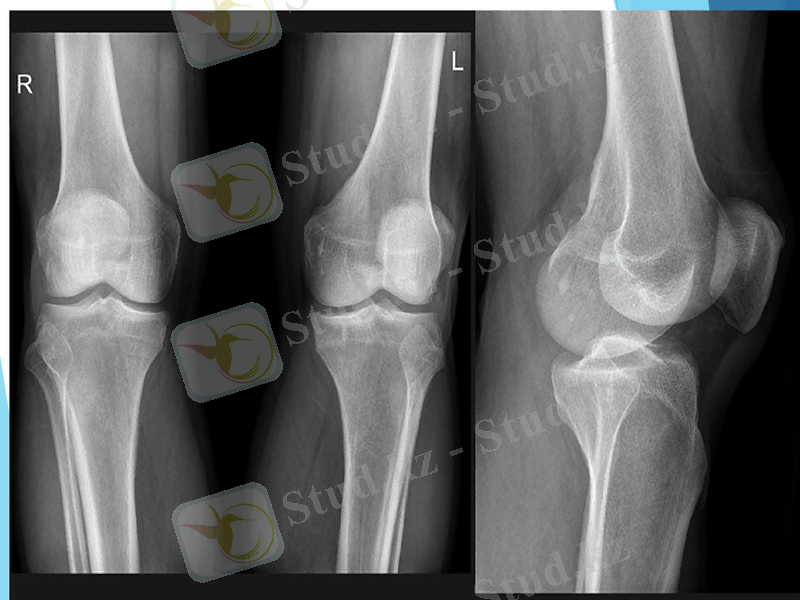

Тізе туберкулезі (гонит)

Туберкулезді гонит сүйек-буын туберкулезінің 15-20%- кездеседі.

Клиникасы туберкулезді кокситке ұқсас келеді. Айырмашылығы тізе буынының ісігі айқын көрінеді және буын пішіні ұршық тәріздес болып келеді, бетіндегі тері жабындысы ісікпен кернелгендіктен бозарады. Бұл белгіні ақ ісік деп атайды (tumor alba) .

Зақымдалған сан аймағының тері қатпарлары сау тінге қарағанда қалыңдау

Александров симптомы